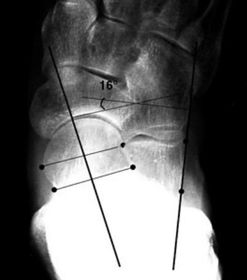

| What angle is this? Is this normal or abnormal? | 1st intermetatarsal angle Abnormal. Greater than 9 degrees is abnormal. Usually due to metatarsus primus varus |